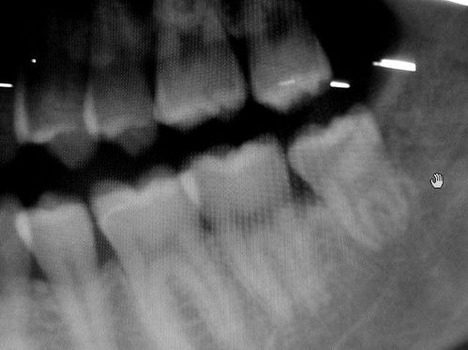

俺の親知らずをレントゲンで見た医者が「とんでもねぇな…」ってつぶやいてたんだけど

下側にある埋伏智歯ね

大きすぎて神経に触ってるから家では抜歯できませんって

●下顎埋伏智歯抜歯に伴う合併症の発生頻度

下あごのもぐっている親知らず(下顎埋伏智歯)の抜歯は、親知らずの抜歯の中では最も合併症をおこす割合が高く、発生頻度は4.3~14.7%(腫れ、痛みを除く)とされています。

ドライソケット(歯槽骨炎)が最も多く、感染、知覚障害(神経損傷、神経麻痺)、出血(血が止まらない)などがおきます。